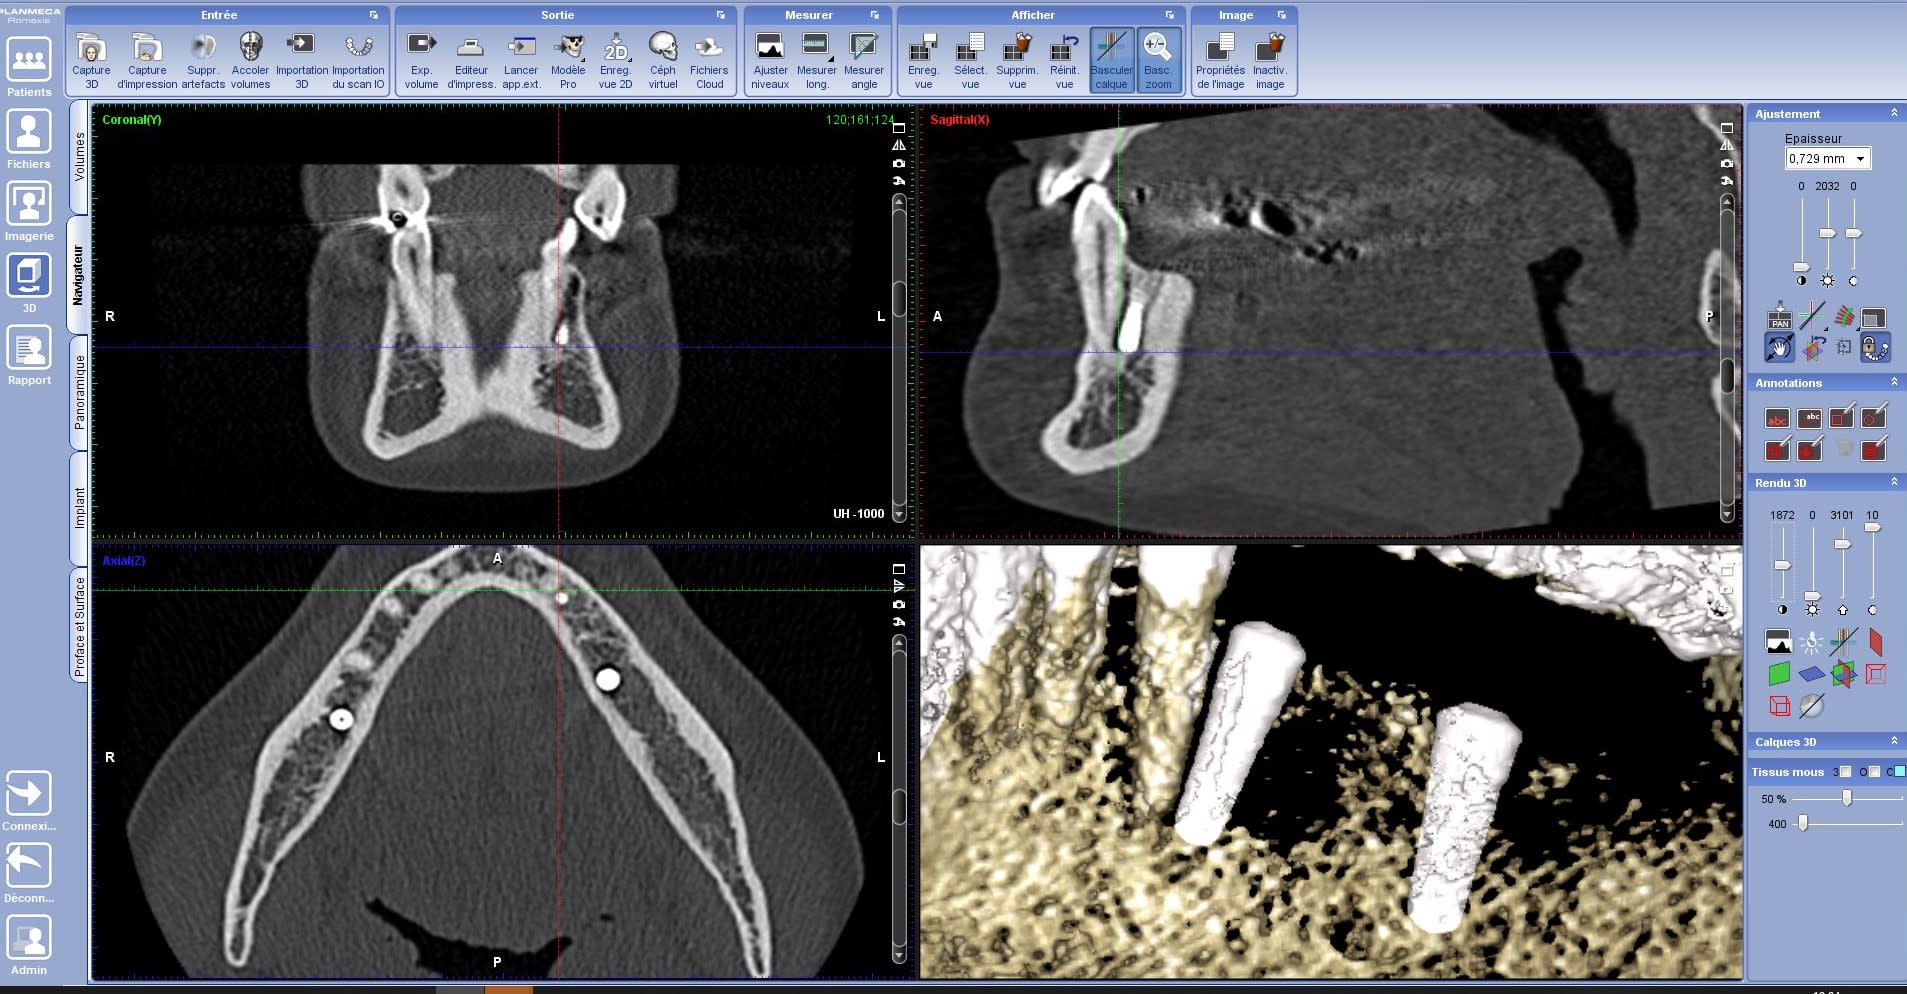

Bonjour à tous, Bon franchement, même avec le scan (qualité médiocre issu du radiologue), ce n'est pas net net... je pense que je suis dedans. Sur la reconstitution 3D, je ne suis pas dedans mais c'est peu fiable et sur les coupe, je ne saurais le dire.

Non mais au vu du scan que j’ai fait passer apres la pose des imp, l’imp est bien au contact de l’apex ! C’est ca qui est fou ! Regardez mon post du 22/10 !